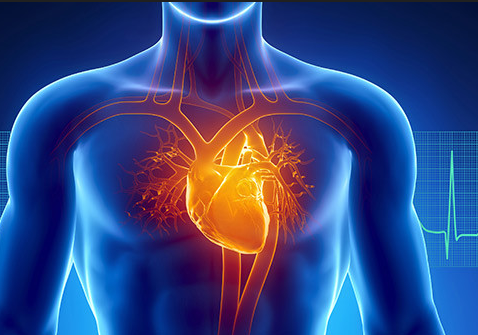

नेपालमा नसर्ने मुटु, क्यान्सर र श्वासप्रश्वास सम्बन्धी रोग धेरै देखिने गरेको छ । नसर्ने रोगबारे काम गरिरहेको संस्था नेपाल एनसिडी एलाइन्सका डा मनिता प्याकुरेलले नेपालमा नसर्ने रोग बढ्दै गएको बताउनुभयो । तीमध्ये मुटु, क्यान्सर र श्वासप्रश्वास सम्बन्धी रोग धेरै देखिने गरेको उहाँको भनाइ छ । प्रमुख नसर्ने रोगमा मुटु रोग ३० प्रतिशत, क्यान्सर नौ प्रतिशत र दीर्घकालीन श्वासप्रश्वास सम्बन्धी रोग १० प्रतिशत रोग लाग्ने गरेको उहाँले बताउनुभयो । नेपालमा आजभन्दा १५ वर्ष अघि अर्थात् सन् २०१० मा कुल मृत्युमध्ये ५१ प्रतिशत नसर्ने रोगबाट हुने गर्दथ्यो । सन् २०१४ मा मृत्युको सङ्ख्या बढेर ६० प्रतिशत पुगेको र सन् २०१६ मा त झन् बढेर ६६ प्रतिशत पुगेको जनाइएको छ । सन् २०१९ मा आइपुग्दा कुल मृत्युको ७१ दशमलव एक प्रतिशत हिस्सा नसर्ने रोगको भागमा परेको ग्लोबल बर्डेन अफ डिजिजको प्रतिवेदनमा उल्लेख छ ।

नसर्ने रोगको उपचारमा हुने खर्च अत्यधिक हुने गर्दछ र स्वास्थ्य क्षेत्रमा हुने कुल खर्चमध्ये सबैभन्दा बढी खर्च नसर्ने रोगमा नै हुने गरेको देखिएको छ । विश्वमा नसर्ने रोगका कारण वार्षिक ४३ लाख व्यक्तिको मृत्यु हुने गरेको छ । विश्व स्वास्थ्य सङ्गठनले सन् २०५० सम्ममा विश्वव्यापी मृत्यु गराउने पाँच प्रमुख कारण नसर्ने रोग नै हुने अनुमान गरेको छ । नसर्ने रोग धुम्रपान तथा सुर्तीजन्य पदार्थको सेवन, अस्वस्थकर खानपान, शारीरिक निष्क्रियता, मद्यपान र वायु प्रदूषणले निम्त्याउने गरेको छ । एलाइन्सका सदस्य तथा स्वास्थ्य पत्रकार सरोज ढुङ्गेलले सरकारले नसर्ने रोगबारेमा आमनागरिकलाई समयमा सचेत गराउन आवश्यक रहेको बताउनुभयो । स्वास्थ्य पत्रकार मञ्च नेपालका पूर्व अध्यक्ष रामप्रसाद न्यौपानेले नसर्ने रोगको रोकथाम र नियन्त्रण गर्न सरकार जतिकै भूमिका पत्रकारको हुने भएकाले नसर्ने रोगबारेमा समाचार सम्प्रेषण गर्न आग्रह गर्नुभयो ।